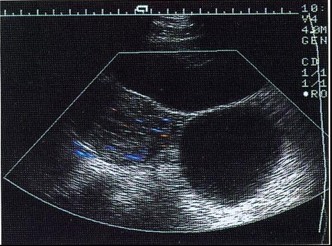

图2 子宫左侧一圆形囊肿,壁薄光滑,囊液清亮